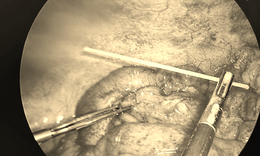

Người đàn ông bị sốc nhiễm trùng, thủng đại tràng do xương cá

Y tế - 30/09/2022 18:05SKĐS - Nam bệnh nhân bị sốc nhiễm trùng, thủng đại tràng nên các bác sĩ Khoa Gây mê hồi sức, Bệnh viện Nhân dân Gia Định phải tích cực điều trị để ổn định sinh hiệu cho người bệnh.